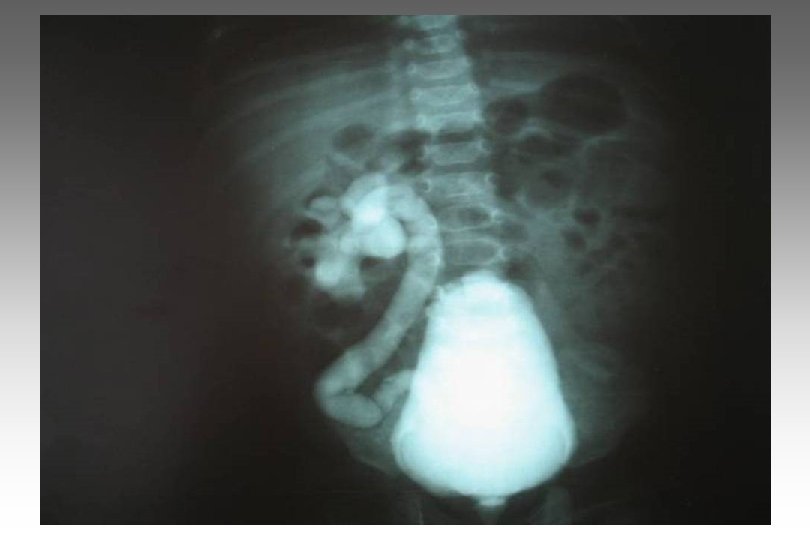

SECUENCIA DE IMAGEN o ECOGRAFIA. o CISTOURETROGRAFIA RETROGADA POST MICCIONAL. o PIELOGRAFIA ENDOVENOSA o GAMMAGRAFIA RENAL CON DMSA-TC 99. o RADIORENOGRAMA o UROGRAFIA POR RMN o TAC HELICOIDAL o ENDOSCOPIA VIRTUAL